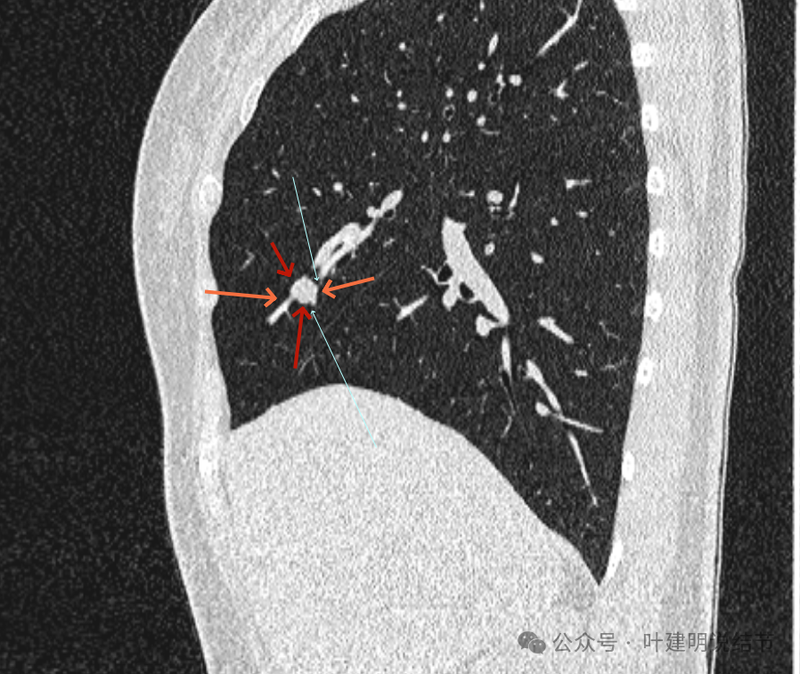

再看冠状位影像:

血管与病灶的关系,两者密度稍不同,天蓝色细箭头所指是分界线。

血管征明显。

血管围着病灶,病灶有膨胀性,表面欠平滑。

不而有膨胀性,血管贴着并被压迫。

边缘欠平滑,邻近血管间隙欠清晰。

血管贴着,结节膨胀。

也示血管与病灶的关系。

结节实性。

纵隔窗这个角度明显见到蓝色箭头所指的血管被病灶侵蚀,而且血管与病灶密度的不同。